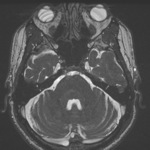

Neck

Soft tissue (MR)

Axial